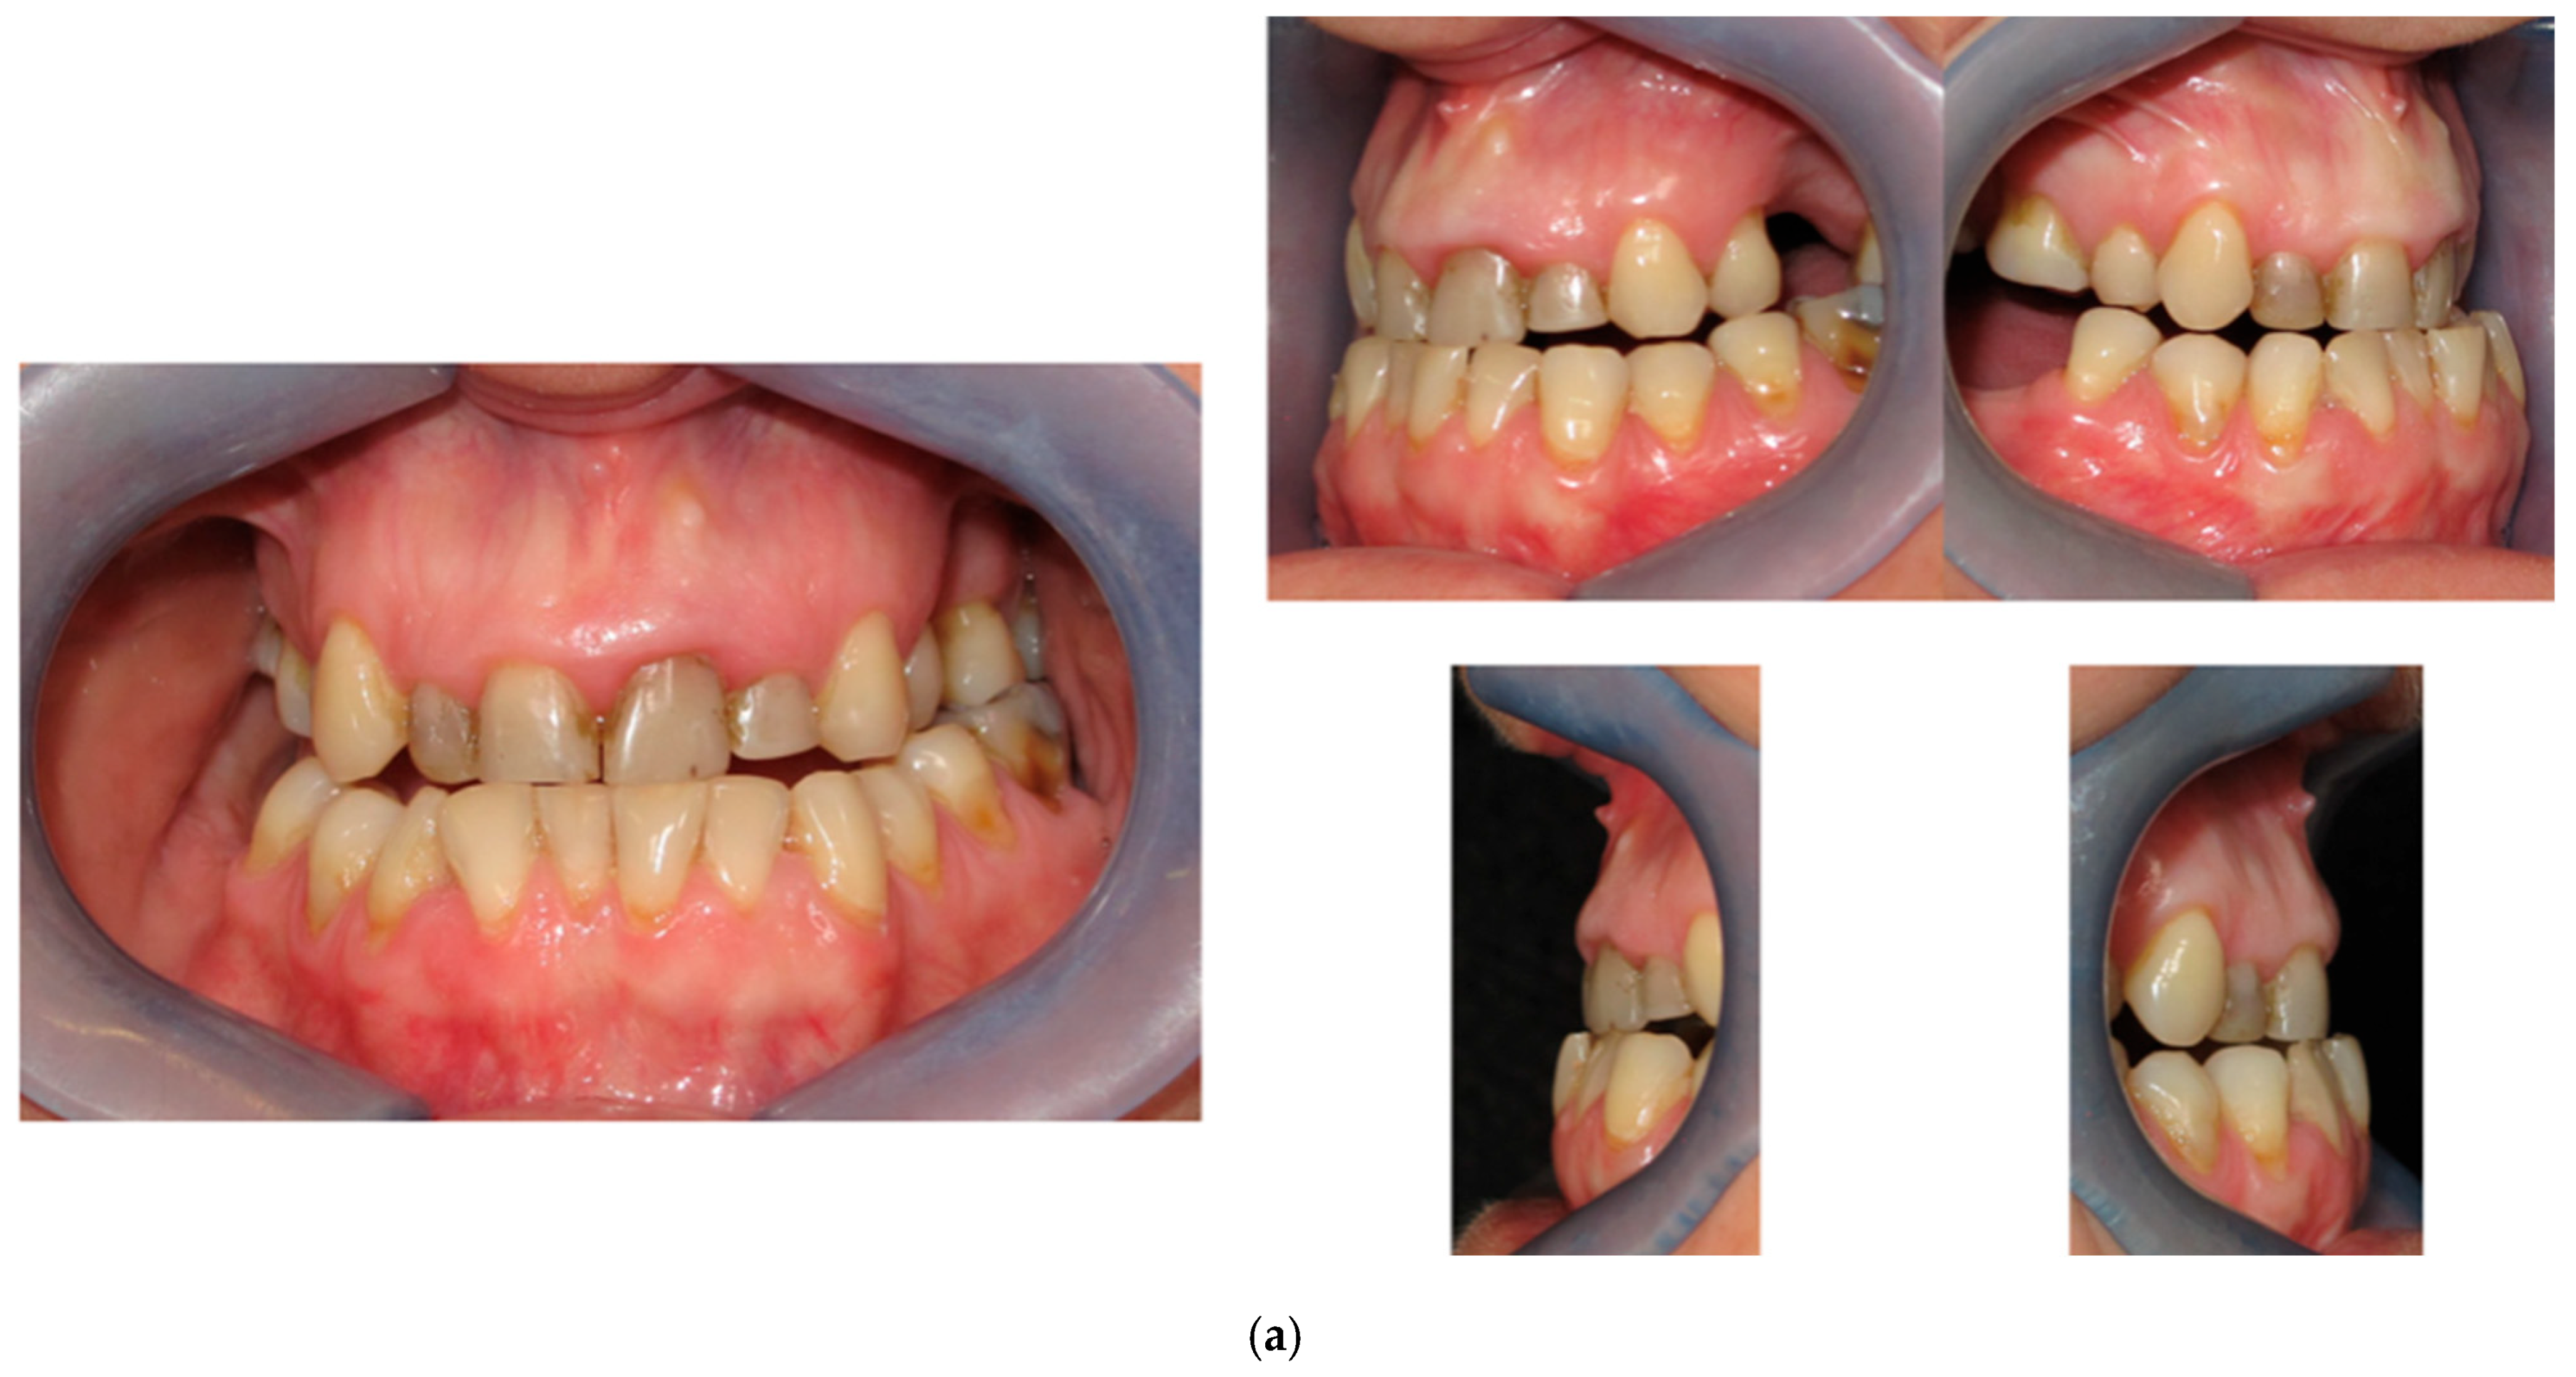

2.1. Patient’s Complaint

2.2. Case History